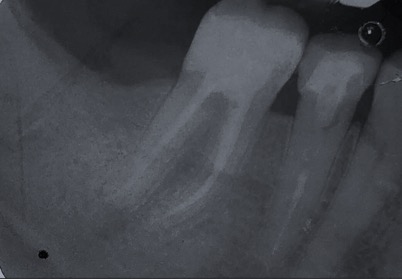

Un trattamento endodontico consiste nel salvare un dente compromesso da carie, traumi o fratture rimuovendone polpa e nervi infetti/infiammati responsabili di dolore, ascessi, cisti e granulomi.

Una corretta terapia canalare con un perfetto sigillo a livello degli apici delle radici è fondamentale. I denti devitalizzati impropriamente possono creare ulteriori problemi che poi andranno a ripercuotersi sulle cure effettuate successivamente come le ricostruzioni e le corone protesiche con conseguente fallimento del piano terapeutico.